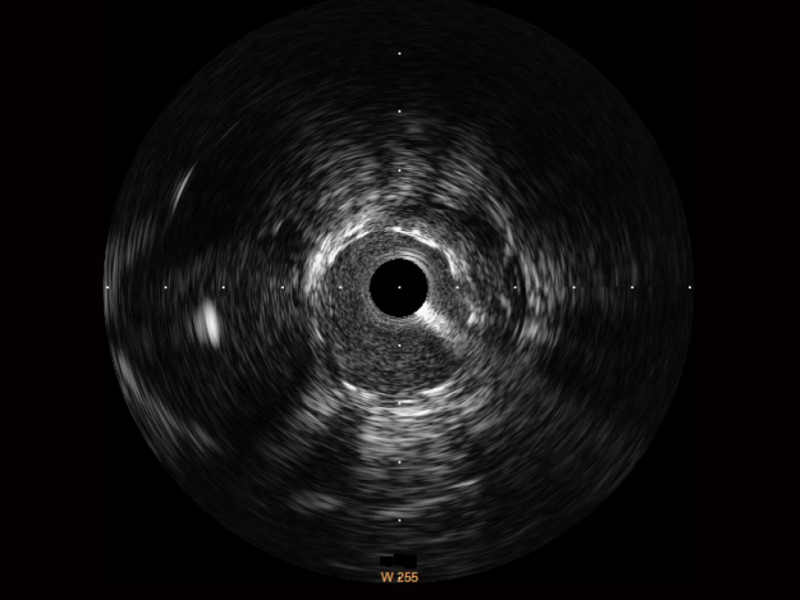

治疗前后两次测量录像对比

简化疗效评估

一键智能描迹,自动测量斑块负荷、面积狭窄率等指标,准确率高于90%